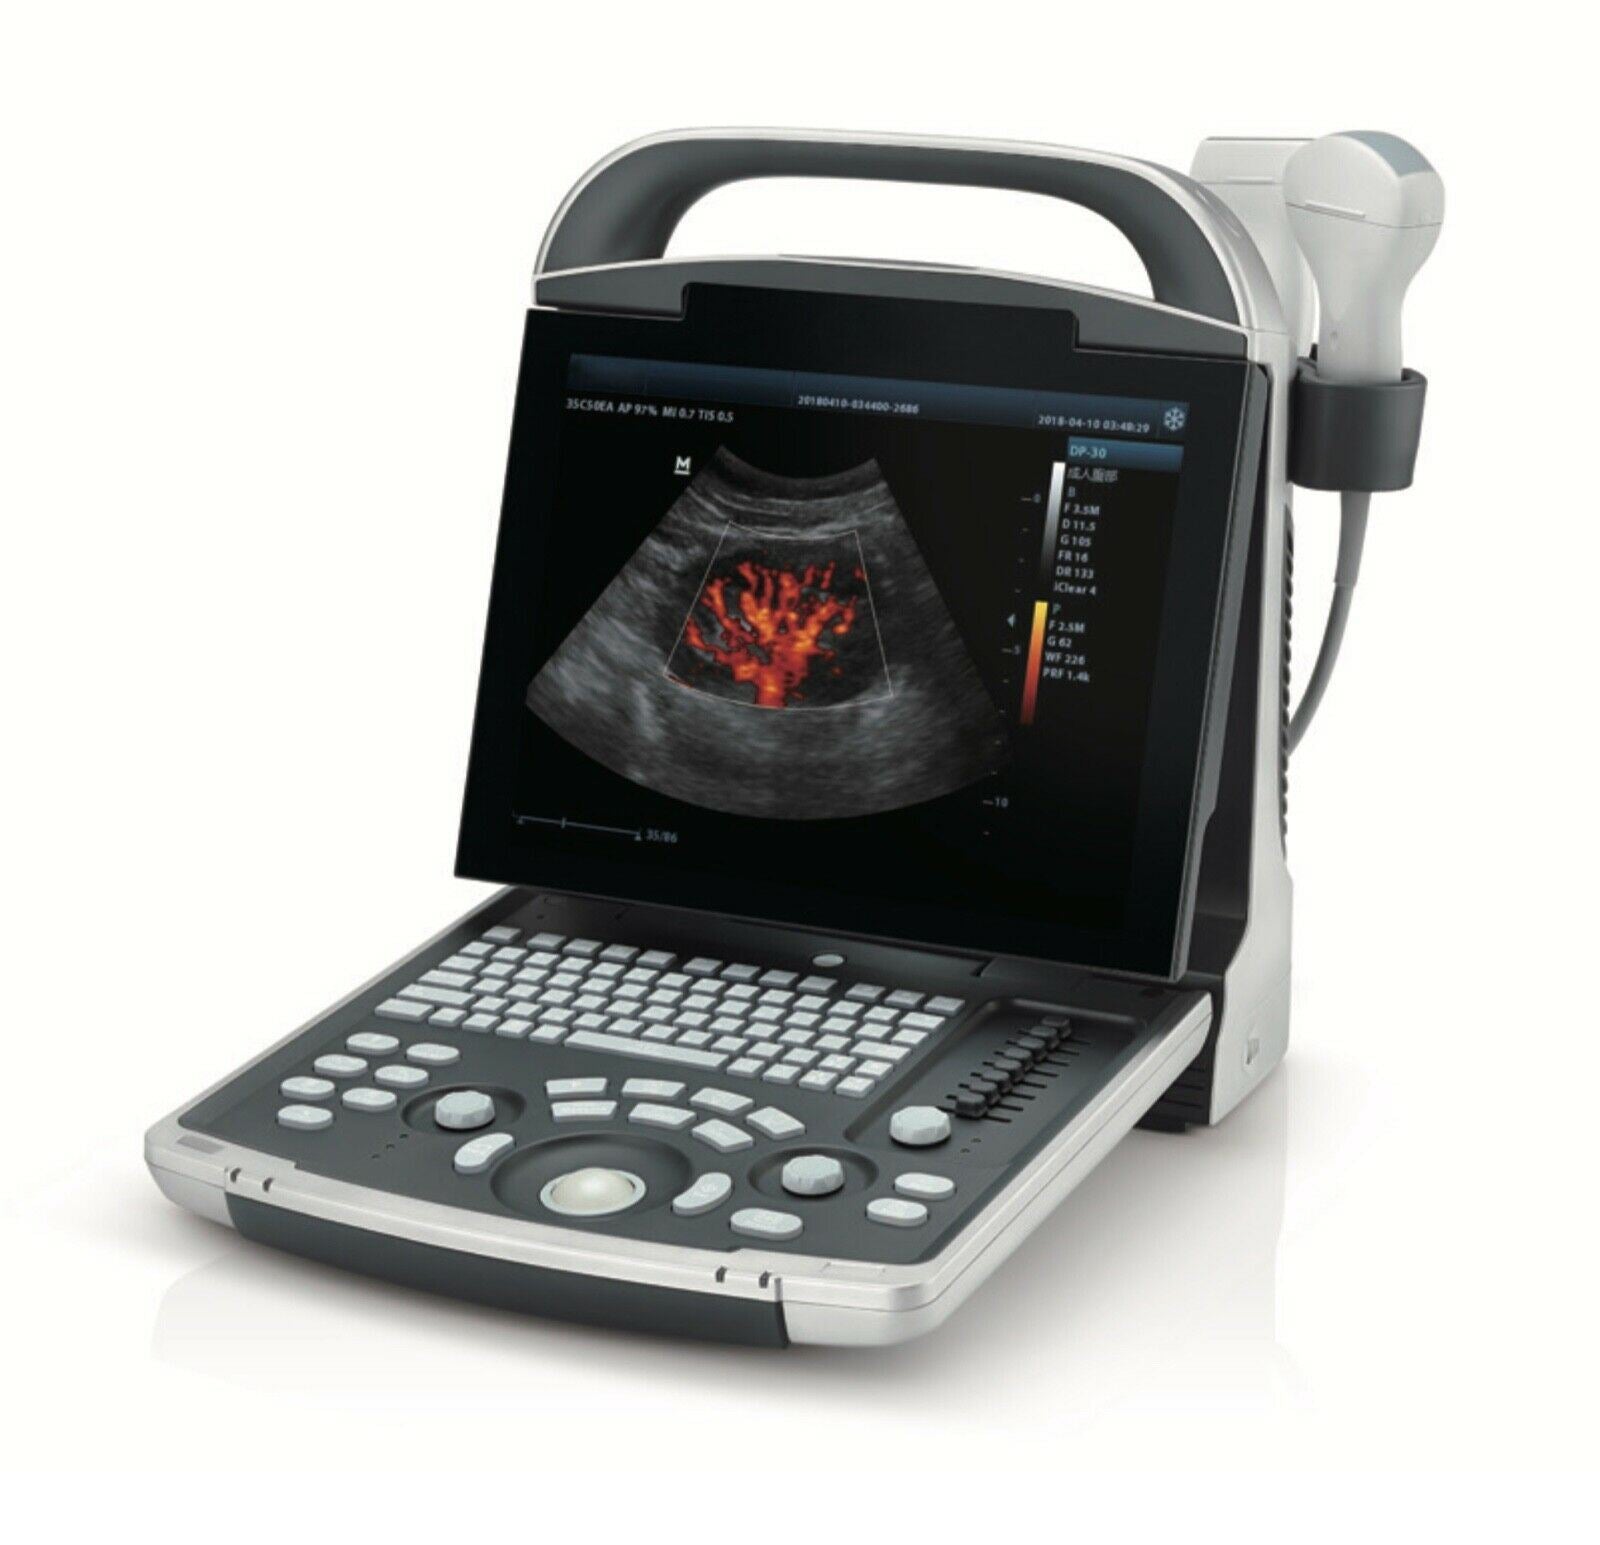

Most Affordable Color Doppler Ultrasound with One Probe LED,THI

- 12.1“ LED monitor, High-Resolution 1024 x 768

Image Quality Beyond Your Expectations

- Optional power Doppler and PW Mode

- Tissue Harmonic Imaging (THI)

- Tissue Specific Imaging (TSI): Optimizing Image Quality Based on Tissue Properties

- One-Button Image Optimization

- 8 Segment TGC Assuring Accurate Image Adjustment

- Versatile Applications with Multiple Transducers

Exceptional Ergonomics & Powerful Workflow

- Compact, Lightweight Design For Enhanced Mobility

- Durable, Comfortable Transducers For Multi-Modality

- Li-ion Battery - 1.5 Hours Scanning Time